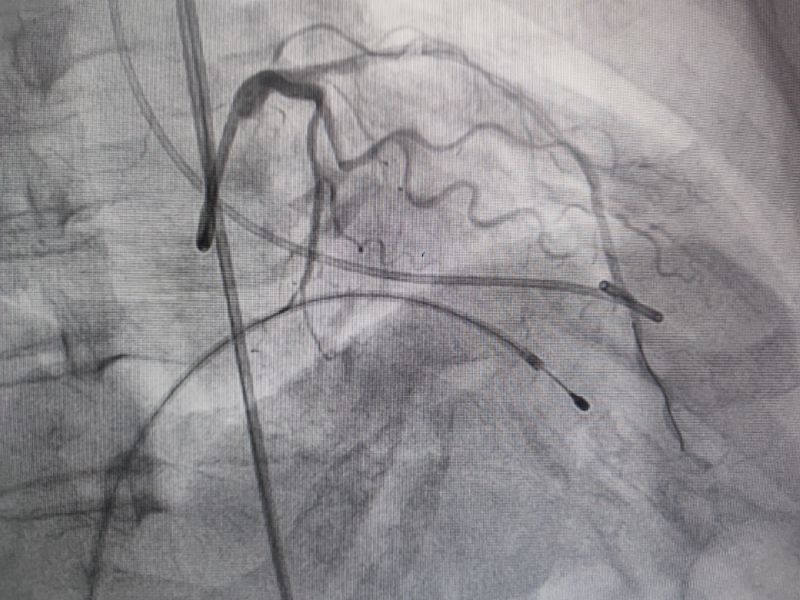

消融后造影

測(cè)壓

消融時(shí)測(cè)壓

經(jīng)過(guò)多輪嚴(yán)謹(jǐn)?shù)男g(shù)前討論,在吳棟梁院長(zhǎng)的專業(yè)指導(dǎo)下,崔旭輝主任醫(yī)師團(tuán)隊(duì)決定在臨時(shí)起搏器的安全保護(hù)下,為患者實(shí)施冠狀動(dòng)脈造影術(shù)及室間隔化學(xué)消融術(shù)。術(shù)中,團(tuán)隊(duì)通過(guò)造影精準(zhǔn)鎖定第一穿隔支為消融靶血管。測(cè)壓數(shù)據(jù)顯示:左室壓260/15mmHg,流出道173/6mmHg,主動(dòng)脈壓106/70 mmHg,壓力階差達(dá)87mmHg。隨后,團(tuán)隊(duì)使用2.0X15mm預(yù)擴(kuò)球囊以8atm壓力阻斷第一穿隔支遠(yuǎn)端血流1分鐘,再次測(cè)壓時(shí),壓力從269/7mmHg驟降至174/4mmHg,這一結(jié)果充分證實(shí)該血管正是室間隔的有效供血血管。緊接著,團(tuán)隊(duì)通過(guò)SPRINTER OTW2.0×8mm球囊緩慢注入1.4ml無(wú)水酒精。10分鐘后復(fù)測(cè),左心室壓降至136/5 mmHg,主動(dòng)脈壓為112/93 mmHg。術(shù)后第2天,王女士胸悶、氣短、心悸等不適癥狀完全消失。復(fù)查心臟彩超顯示:EF值與FS值保持穩(wěn)定,收縮期左室流出道血流速度降至252cm/s,PG值為25mmHg。